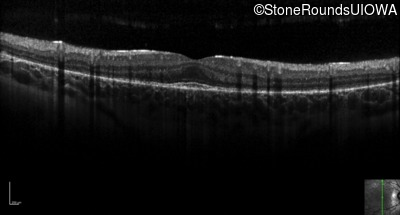

Optical Coherence Tomography - Left - 20/25 -3

Exemplar / OCT Stack